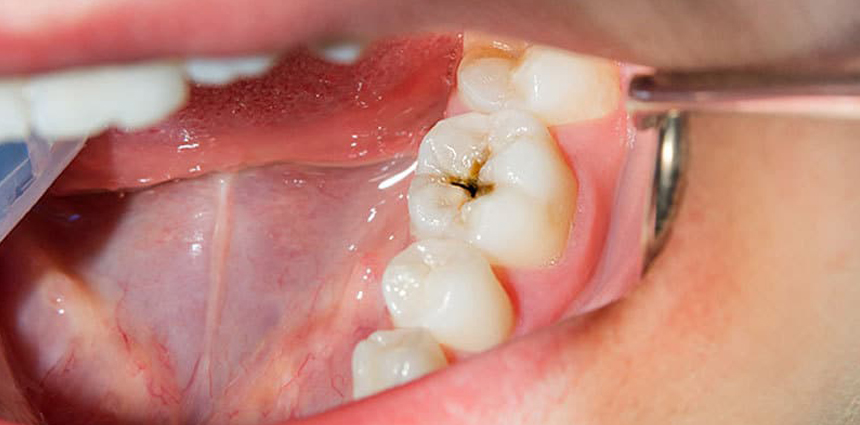

Bacterial infection

Bacteria can get into the pulp of a tooth through small openings created by tooth decay or injury. Inflammation or a bacterial infection of the pulp is the most common reason people see an endodontist.